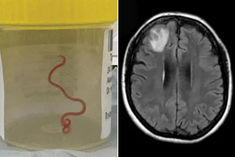

For first time ever, doctors remove 8-centimetres-long roundworm during brain surgery in Australia